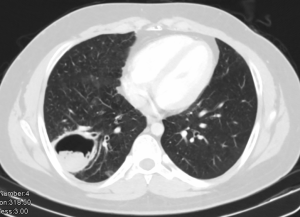

Pulmonary aspergillosis can manifest as invasive aspergillosis, allergic bronchopulmonary aspergillosis (ABPA) or cavitary pulmonary aspergillosis (Figures 4,5). In tuberculosis endemic countries of the world, the healed tubercular cavities act as the much needed nidus for saprophytic colonization of Aspergillus fumigatus. The fungal toxins erode the tissues and can cause haemoptysis when a vessel wall is eroded. Presence of the characteristic fungal ball with ‘air crescent’ in chest X-ray or CT scan clinches the diagnosis. Surgery in the form of pulmonary resection is the mainstay of treatment although intraoperative period can be complicated by dense intra-pleural adhesions, hemorrhage, air leak, disruption of cavity and seeding of the fungus with high morbidity (13-15). Surgical mortality ranges from 0% to 22.6% and reported recurrence rate is 5% (16).